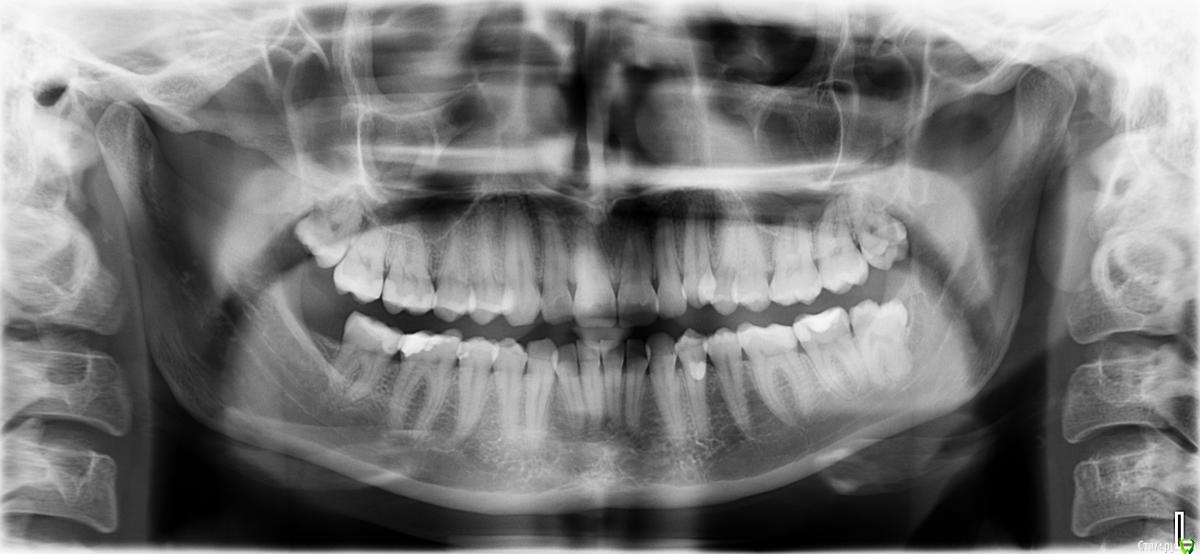

Добрый день! Подскажите пожалуйста,в феврале обратилась к стоматологу,залечили 5,6,7 зуб справа. 8-на удаление. снимок не делали.

Через несколько дней 6 или 7 зуб стал реагировать на сладкое,холодное. от сладкого сводит всю челюсть верхнюю. Боли проходят,если прополоскать теплой водой.Через неделю мне удалять 8-ку ,если дело не в ней,хотелось бы разобраться сначала с этими зубами. В каком зубе причина?

post-51277-0-74225400-1492005802_thumb.jpg